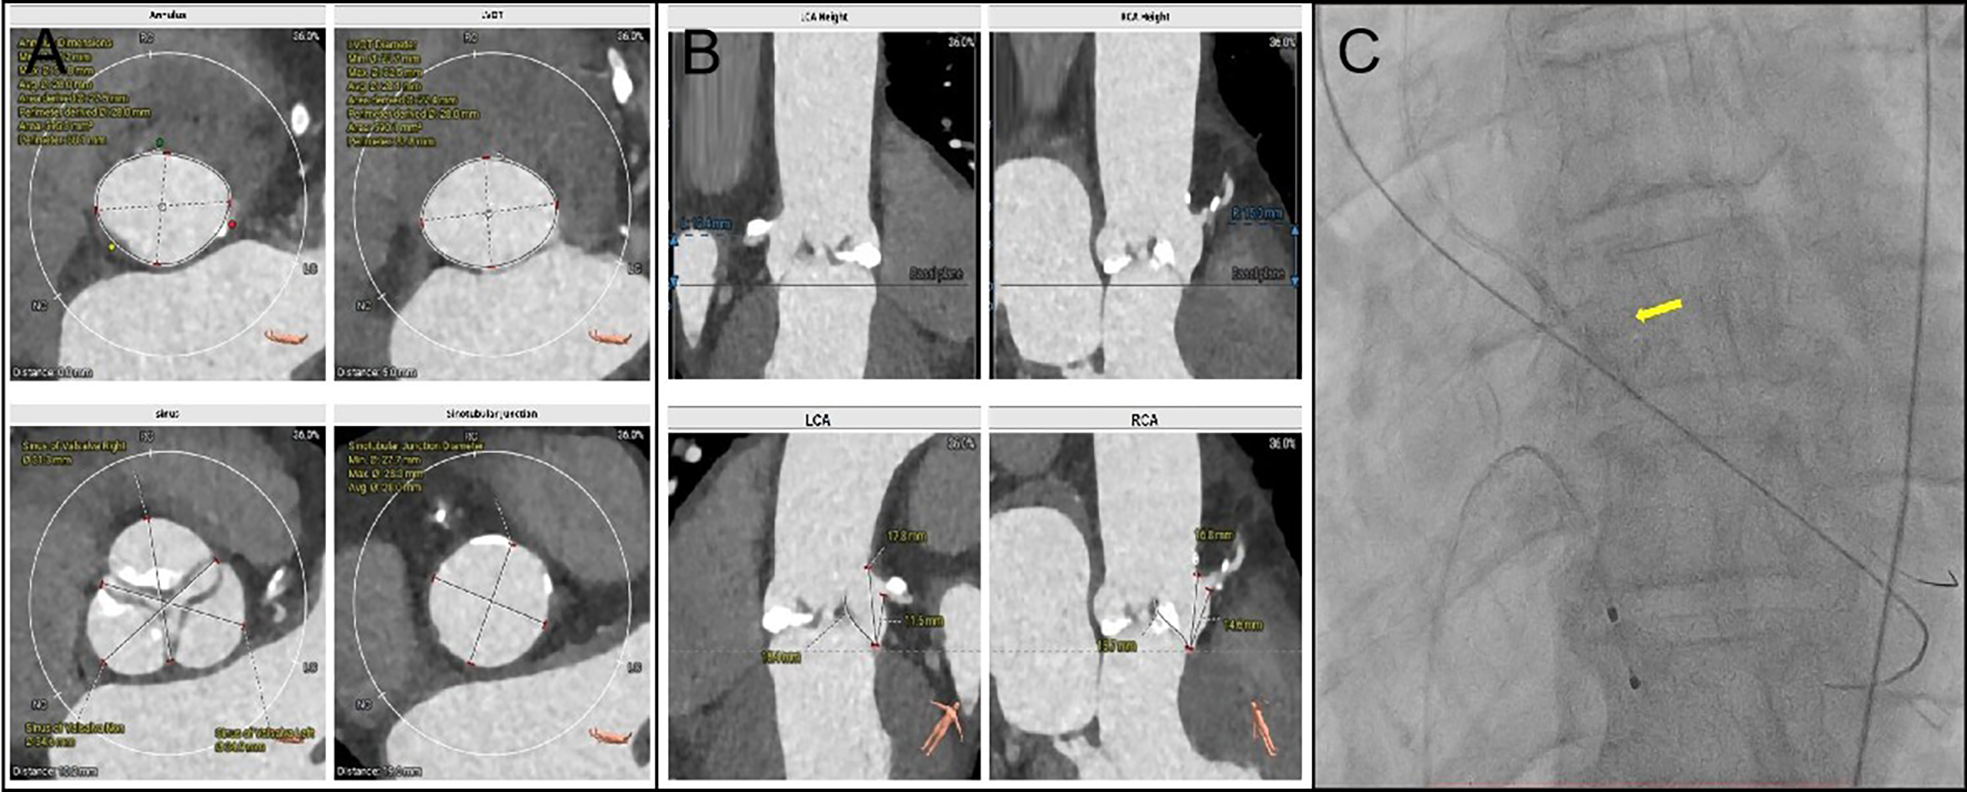

A 69-year-old male diagnosed with severe aortic valve stenosis and NYHA IV heart failure symptoms was admitted to the Department of Cardiology, Second Affiliated Hospital of Harbin Medical University. The preoperative computed tomography evaluation revealed accessible femoral artery entry points, with the valve annulus area and perimeter recorded at 595.3 mm2 and 88.1 mm, respectively, suitable for a 32 mm VenusA Valve implantation (Figures 1A,B). The coronary artery CTA identified proximal stenosis in both the left main stem and the right coronary ostium (Supplementary Figure S1). Following discussions and the patient's refusal of surgical intervention, it was agreed to proceed with a combined single-stage surgery of coronary PCI and transfemoral TAVR (The patient was instructed to take 300 mg of aspirin and 300 mg of clopidogrel prior to the surgery). With the patient's consent, Firebird 2 stents were placed in the right coronary artery and left main stem, and a 32 mm VenusA Valve was implanted.

Figure 1

(A): Annulus dimensions Min: 24.2 mm; Max: 31.8 mm; Avg: 28.0 mm; Area derived: 27.5 mm; Perimeter derived: 28.0 mm; Area: 595.3 mm2; Perimeter: 88.1 mm. LVOT Diameter Min: 23.7 mm; Max: 32.5 mm; Avg: 28.1 mm; Area derived: 27.4 mm; Perimeter derived: 28.0 mm; Area: 590.1 mm2 and Perimeter: 87.8 mm. Sinus of valsalva Left: 34.9 mm; Sinotubular Junction Diameter Min: 27.7 mm; Max: 28.3 mm and Avg: 28.0 mm. (B) LCA Heigh 12.4 mm. Left Leaflets Length: 15.4 mm. (C) The PILOT 200 wire managed to cross the valve, followed by a 4.0 mm × 15 mm balloon to dilate the aortic valve. The yellow arrow is the balloon.

The procedure was conducted under conscious sedation. Initial the standard straight-tip crossing wire could not traverse the valve, and the 6F AL1 catheter could not be advanced due to wire displacement during repeated efforts. Success was achieved by re-crossing the valve and switching to a 5F AL1 catheter, which allowed entry into the left ventricle. Despite changing to a J-tip wire, the 5F pigtail catheter still failed to progress into the left ventricle. Adopting a radial artery approach, the PILOT 200 wire managed to cross the valve, followed by a 4.0 mm × 15 mm balloon to dilate the aortic valve, which allowed the pigtail catheter to enter the left ventricle successfully (Figure 1C).